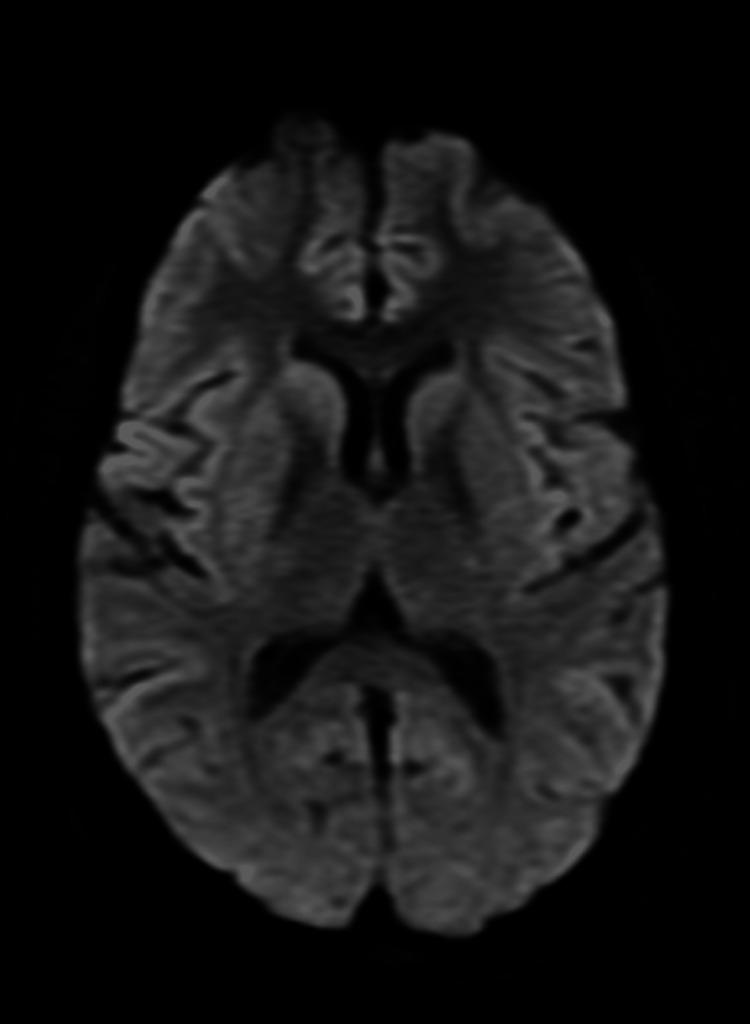

后部可逆性脑病综合征(PRES)的非典型表现:一例病例报告及文献复习

Atypical Presentation of Posterior Reversible Encephalopathy Syndrome (PRES): A Case Report and Review of the Literature.

Posterior reversible encephalopathy syndrome (PRES) is a reversible clinico-radiological entity characterized by acute neurological symptoms and white matter vasogenic edema that commonly affects the posterior occipital and parietal lobes of the brain. Patients with this condition usually present with complaints of headache, encephalopathy, seizures, or visual disturbances. Nystagmus and periodic alternating gaze are rarely reported presentations of PRES patients. Similarly, involvement of the brainstem, cerebellum, basal ganglia, and other cerebral areas are atypical findings on brain imaging. Early diagnosis and immediate treatment can reverse both the clinical and radiological features of PRES.

摘要

后部可逆性脑病综合征(PRES)是一种可逆的临床放射学实体,其特征为急性神经症状和白质血管源性水肿,通常影响大脑的枕叶后部和顶叶。患有这种疾病的患者通常会出现头痛、脑病、癫痫发作或视觉障碍等症状。眼球震颤和周期性交替凝视是PRES患者很少见的表现。同样,脑干、小脑、基底神经节和其他脑区受累在脑部影像学检查中属于非典型表现。早期诊断和及时治疗可使PRES的临床和放射学特征得到逆转。